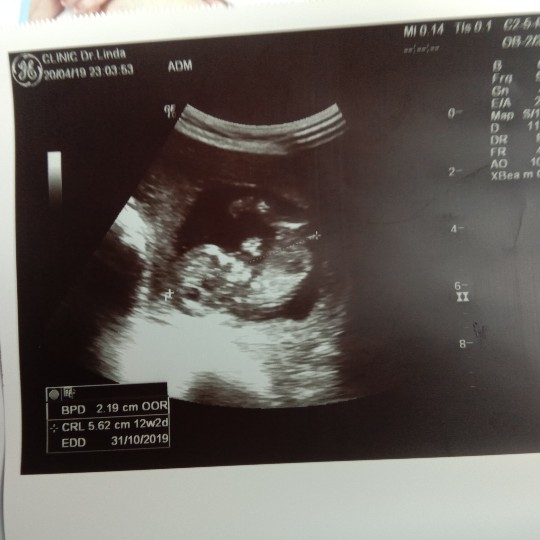

12wค่ะ